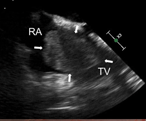

Surgical management of a giant right atrial myxoma

Jeesoo Choi and others

Journal of Surgical Case Reports, Volume 2018, Issue 10, October 2018, rjy288, https://doi.org/10.1093/jscr/rjy288